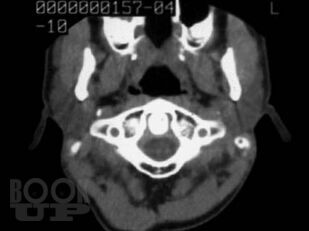

Монография основана на результатах исследований в отделении лучевой диагностики Института хирургии им. А.В. Вишневского РАМН. Представлена методика спиральной КТ шеи с внутривенным болюсным контрастным усилением. Изучена КТ-семиотика образований в нативную, артериальную, венозную и отсроченную фазы исследования. Представлены способы построения реконструкций (3D и MPR) патологических образований и структур шеи. Показаны возможности и эффективность нативной фазы КТ-исследования в диагностике липом и боковых кист шеи. Обоснована необходимость внутривенного усиления для выявления озлокачествления боковых и срединных кист. Значительная часть монографии посвящена дифференциальной диагностике объемных образований в области развилки сонных артерий: каротидных и вагальных хемодектом, неврином, исходящих из блуждающего нерва и симпатического ствола, а также аневризм сонных артерий. Показана возможность оценки взаимоотношения хемодектом с внутренней сонной артерией. Также оценена положительная сторона динамической КТ с внутривенным болюсным усилением в дифференциальной диагностике объемных образований шеи, и указаны ее недостатки в оценке взаимоотношения опухоли с сонными артериями на протяжении. При контрастном усилении выявлены дифференциальные КТ-признаки конгломерата лимфоузлов и первичных опухолей. Описаны некоторые редко встречающиеся опухоли и деформации шеи, симулирующие опухоли.